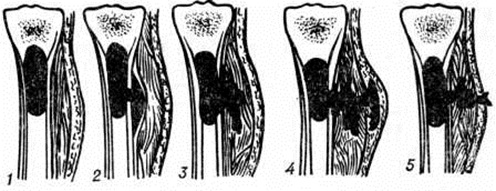

В ходе нагноения в окружающих очаг тканях развёртываются пролиферативные и дистрофические процессы. В результате пролиферации тканей возникает гноеродная оболочка, а затем формируется костная мозоль (смотри полный свод знаний) с последующей консолидацией перелома или образуются лишь костные разрастания по краям отломков (рисунок 4). Возникшая костная мозоль включает в себя гнойники с секвестрами (цветной рисунок 2) и играет т. о. роль секвестральной капсулы, из которой свищевые ходы ведут на поверхность кожи (рисунок 5). Дистрофические изменения выражаются в диффузной рарефикации, а позже в очаговой эбурнеации кости (смотри полный свод знаний) в зоне образования мозоли. В окружающих мягких тканях и в соседних суставах развиваются явления атрофии.

Различают ранние и поздние гнойно-воспалительные осложнения огнестрельных переломов костей. Ранние осложнения, возникающие непосредственно после ранения, в большинстве случаев связаны с гнилостным распадом костного мозга или гнойным воспалением его внутри костномозгового канала и характеризуются бурным клинические, течением с выраженными общими реакциями, как и при гематогенном Остеомиелит Поздние осложнения (спустя 1—2 месяцев после ранения) развиваются обычно вне костномозгового канала, главным образом в элементах опорной костной ткани; при этом наблюдается выраженное отграничение процесса и образование гнойной полости вокруг мёртвых костных осколков и инородных тел (рисунок 8). Репаративно-ре генеративные процессы, приводящие к патологический изменениям в виде гиперостоза (смотри полный свод знаний) и склероза плотной костной ткани (смотри полный свод знаний Остеосклероз), составляют сущность этого вида осложнений и обусловливают переход ранних его форм в хронические.

Процесс постепенной секвестрации в ближайшие недели, иногда месяцы, завершается полным отделением некротизированных участков (секвестров) от здоровой костной ткани и образованием костной полости. Величина и форма секвестров может быть различной. При всем их многообразии выделяют следующие виды секвестров: кортикальный (корковый) — при некротизации тонкой костной пластинки под надкостницей; центральный — при омертвении эндостальной поверхности кости; проникающий — при некрозе всей толщи компактного слоя на ограниченном по окружности участке кости; тотальный — при некротизации трубчатой кости по всей её окружности, иногда на протяжении всей кости; циркулярный (венечный) — при некрозе диафиза по всей окружности, но на небольшом участке по длине (секвестр в виде узкого кольца); губчатый — при омертвении спонгиозной ткани длинных трубчатых или плоских костей.

Чаще всего встречаются центральные, кортикальные и проникающие секвестры (рисунок 10). Секвестр может целиком или частично находиться в костной полости или полностью располагаться вне её, в мягких тканях (рисунок 11).